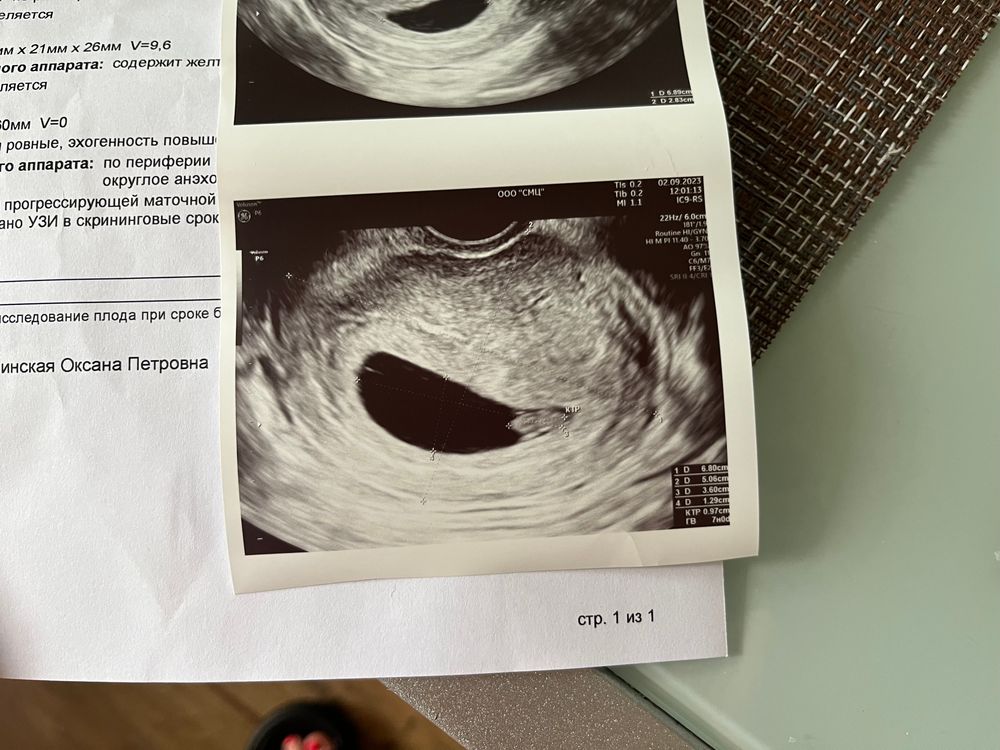

Узи 7 недель

была на узи , врач сказала что сердечко определяется , но ничего не сказала про количество ударов , это нормально ?